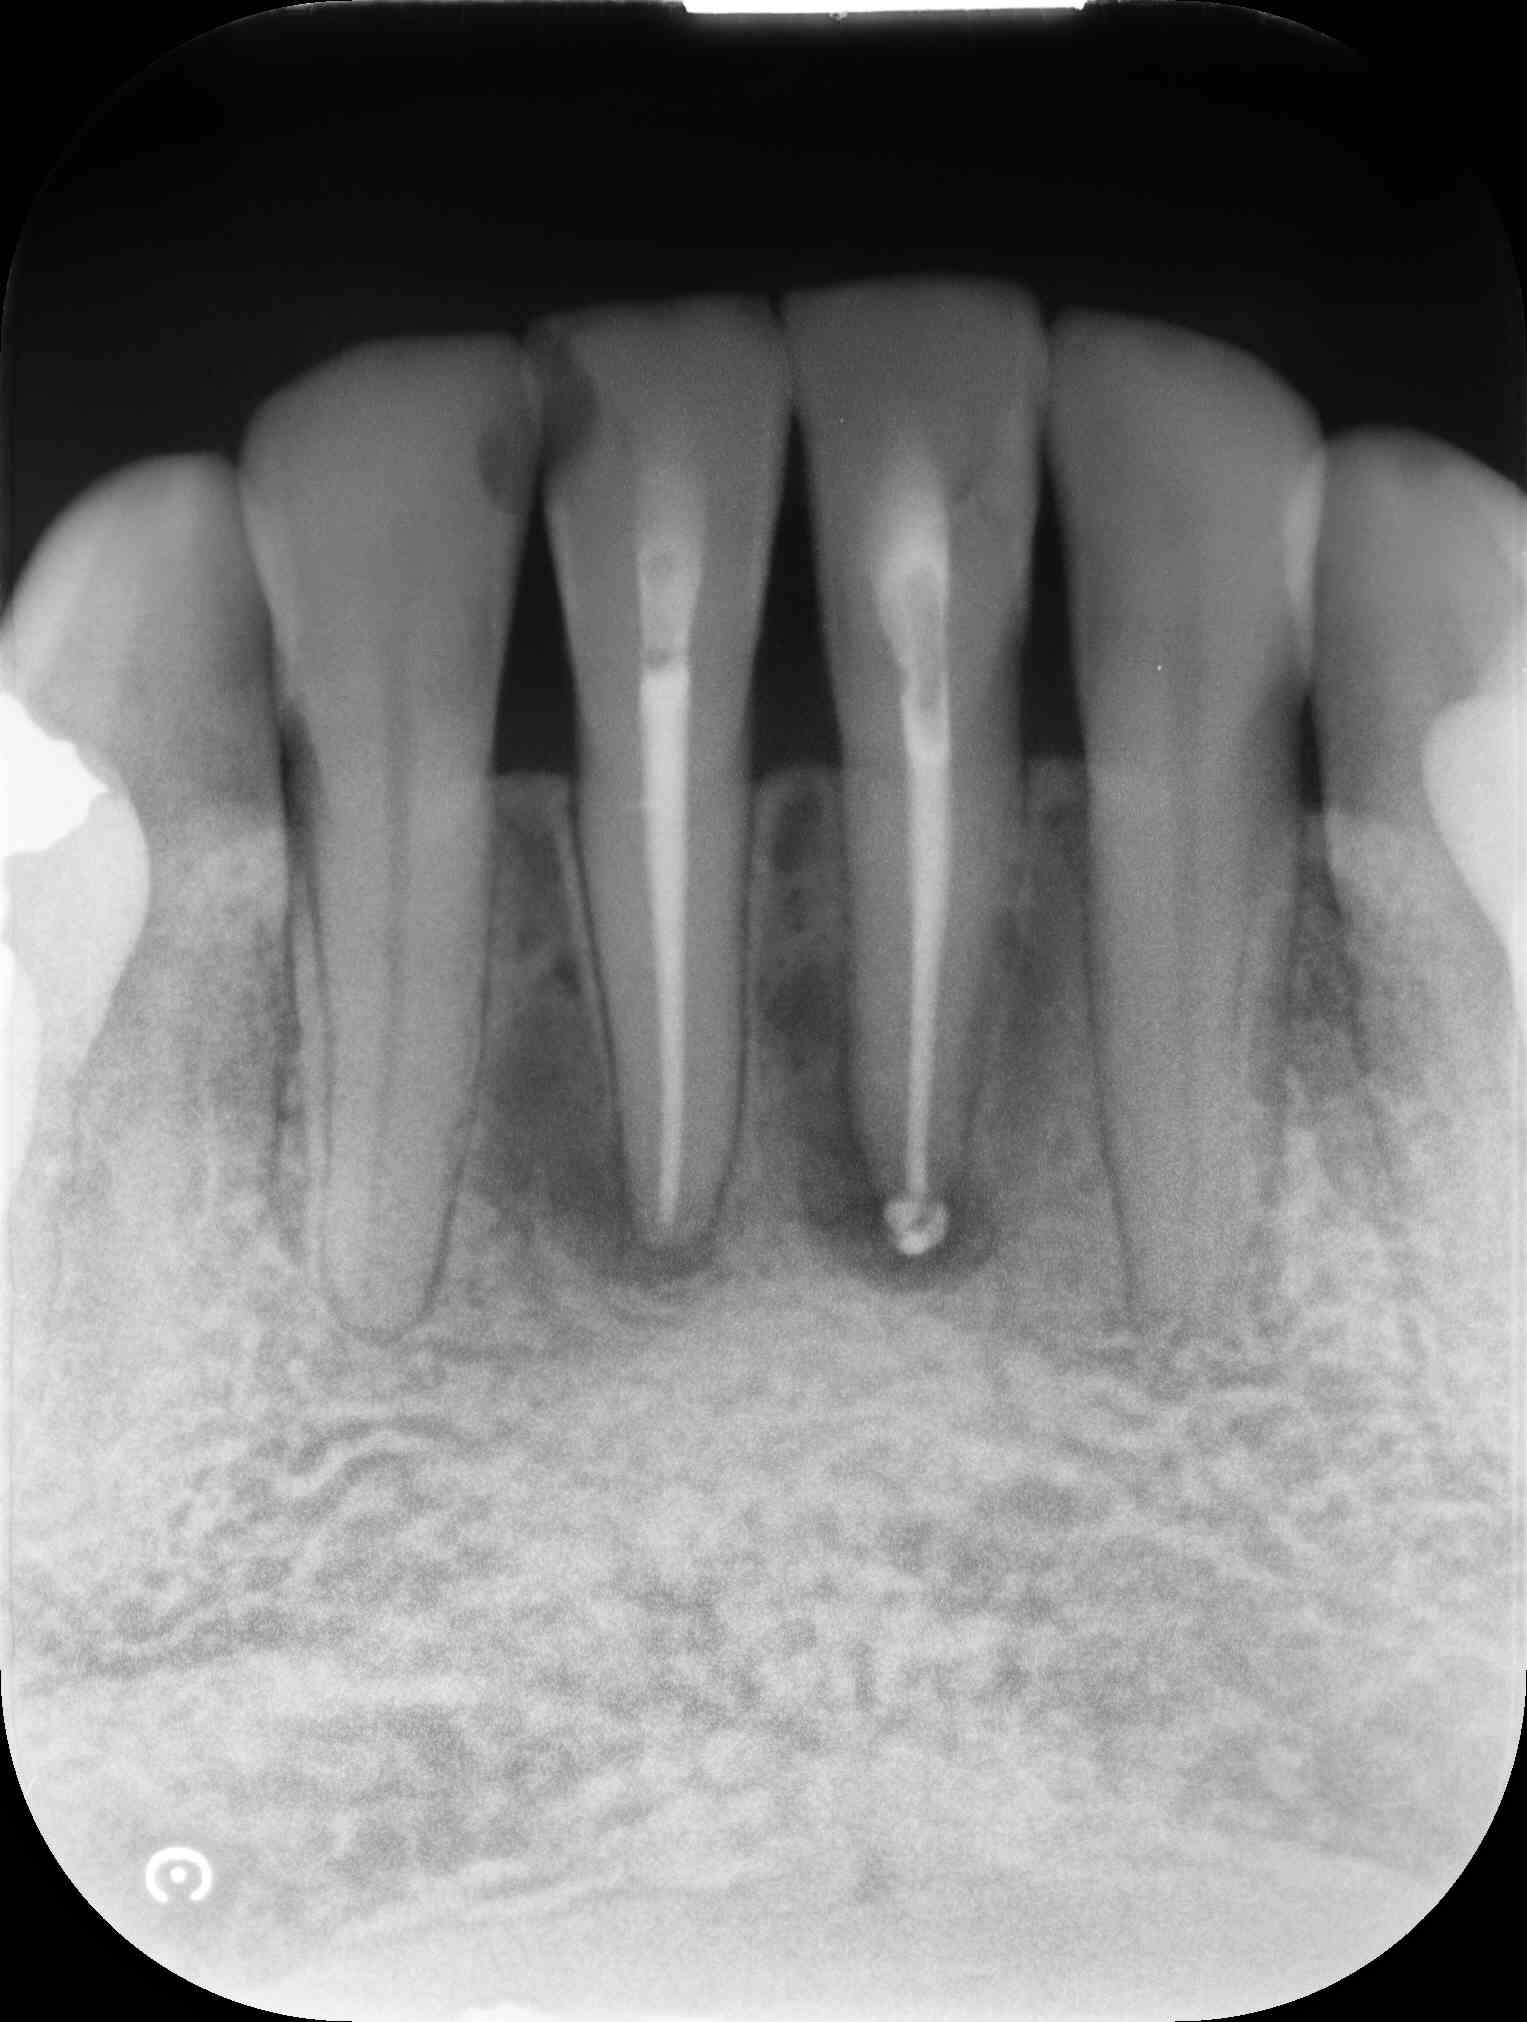

術前のレントゲン写真とCT画像と、お口の中の写真です。下の前歯2本(#31,41)です。

2本の根の周りに黒い影(透過像)があるのが分かります。

術直後のレントゲン写真です。

術後6ヵ月後のレントゲン写真とCT画像です。

術前にあった根の周りの黒い影は縮小して改善しているのが分かります。